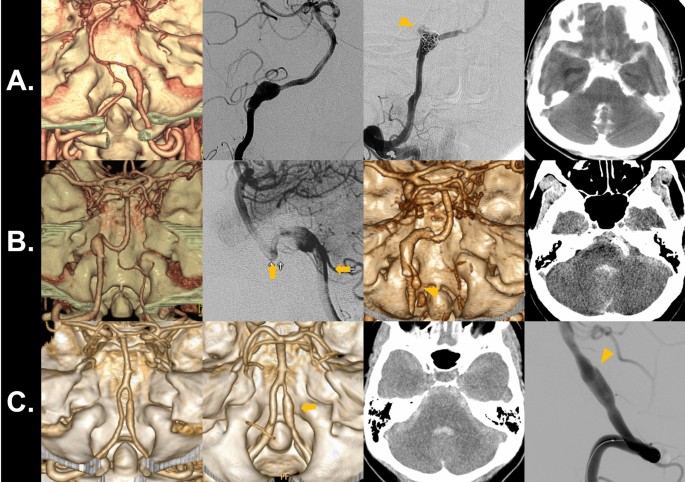

One new SAH event occurred in the concurrent headache group. A woman in her thirties presented with symptoms of lateral medullary infarction (Fig. 2A). CT angiography showed a dissecting aneurysm of the right V4 segment. Immediate IA embolization was planned. However, during embolization, initial guidewire advancement across the dissecting aneurysm resulted in contrast-extravasation (orange arrowhead) and intraprocedural subarachnoid hemorrhage.

Two new SAH event occurred in the isolated headache group. A man in his forties presented with headache and showed a dissecting aneurysm of his left vertebral artery (Fig. 2B). A Neuroform stent (Stryker Neurovascular, Kalamazoo, Michigan) was placed for flow diversion and as a pretreatment prior to coil embolization (orange arrows). It did not result in reduction of aneurysmal size. However, the patient did not agree to further embolization procedures. After 8 years, the patient presented with sudden mental change and SAH bleeding from the dissecting aneurysm (orange arrowhead). Another woman in her fifties presented with headache and dissecting aneurysm of the right vertebral artery (Fig. 2C). She was admitted for observation of the dissecting aneurysm. However, the patient developed sudden headache and coma on the next day. Brain imaging revealed SAH, and a slight enlargement (orange arrow) and lobulated appearance (orange arrowhead) of the aneurysm.